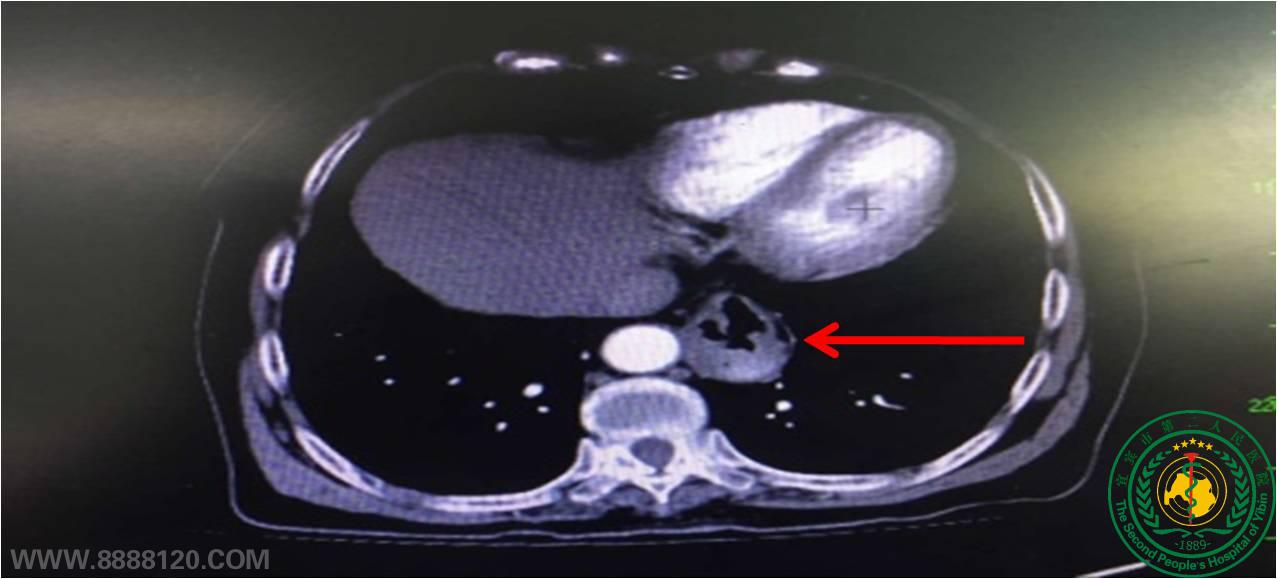

患者卓某,女性,67岁,因“反酸、嗳气伴上腹部胀痛不适3月余”入院,经检查确诊为:反流性食管炎、食管裂孔疝。术前杨朝坤主任医师多次查看病人并为其制定治疗方案,经科室讨论后决定为其施行创伤小、安全性高的腹腔镜下食管裂孔疝修补术、部分胃底折叠术,手术经过非常顺利,该患术后第2天进食,术后第4天出院,出院时反流症状完全消失,复查胸部CT提示食管裂孔区囊袋完全消失

术前CT诊断食管裂孔疝                  术中食管裂孔疝位置              术后食管裂孔疝消失